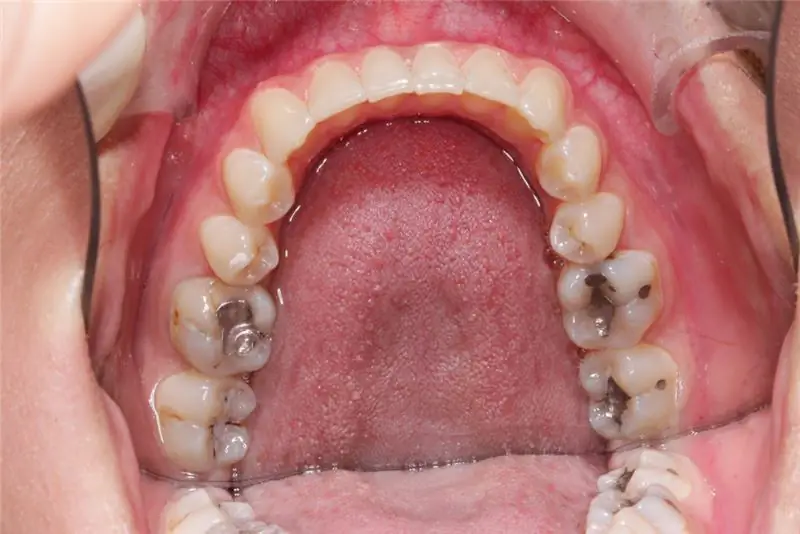

Женщина лечилась у дантиста из Лемго в период с 1987 по 2009 год. С детства у нее было несколько пломб из серебряной амальгамы. Но использовались и золотые пломбы.

Лечение амальгамой было неправильным, сказал пациент. У нее развилась аллергия на амальгаму, которую стоматолог не распознал. Кроме того, у нее во рту был «эффект батарейки». Когда металлы золото и серебро находились во рту, в результате электролиза создавался слабый ток. Другому стоматологу пришлось удалить пломбы из амальгамы, а также вырвать два зуба.

Это также относится к электрохимической реакции из-за использования золота и амальгамы. Потому что используемые амальгамы серебра предотвратят дальнейшие электрохимические реакции при контакте со слюной. Местонахождение остатков амальгамы при наращивании новых золотых коронок также безвредно. Потому что золотые коронки фиксируются цементом, так что между амальгамой и золотом создается необходимая изоляция.